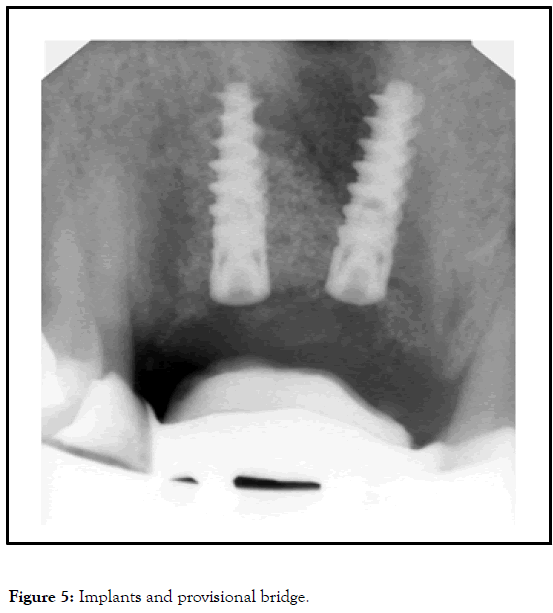

Two implants have been used, Alpha-Bio Neo/3.2 mm, and 13 mm in length (topical anesthesia articain 1/100.000). Reasons for using this implant were one. Primary stability, in the native bone, because of the aggressive threads. Small diameter, possibly I need only the pilot drill. I used piezoelectric surgery for the preparation of the implants wells, in order to avoid vibrations, common with the use of micromotor. As surgical guide, we used a clear copy of the Maryland [14].

The problem was the slight mobility of the graft and the fact that the implants installed with screwing and were taking the final position not coincident with the implant osteotomy, so the distance between them, was slight less than 3 mm.

Some implants, such as those with an aggressive thread design, may change the drilling path and angulation, and this three-dimensional change commonly occurs as the implant is being torqued in place; the implant is following the path of least resistance within the alveolus.

Implant Aesthetics, Keys to Diagnosis and Treatment. The final torque was 40 N*cm, and I had the fear to lose the graft; implants remain in that position (Figures 4 and 5).